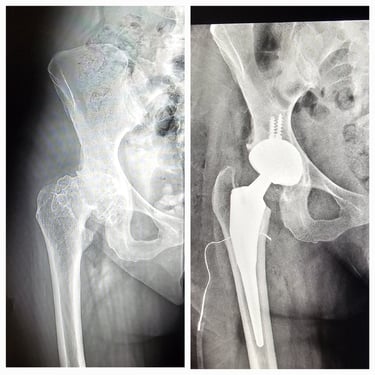

Artroplastia de cadera (prótesis total/parcial).

Cirugía de revisión de cadera y rodilla.

Desgaste articular de cadera y rodilla.